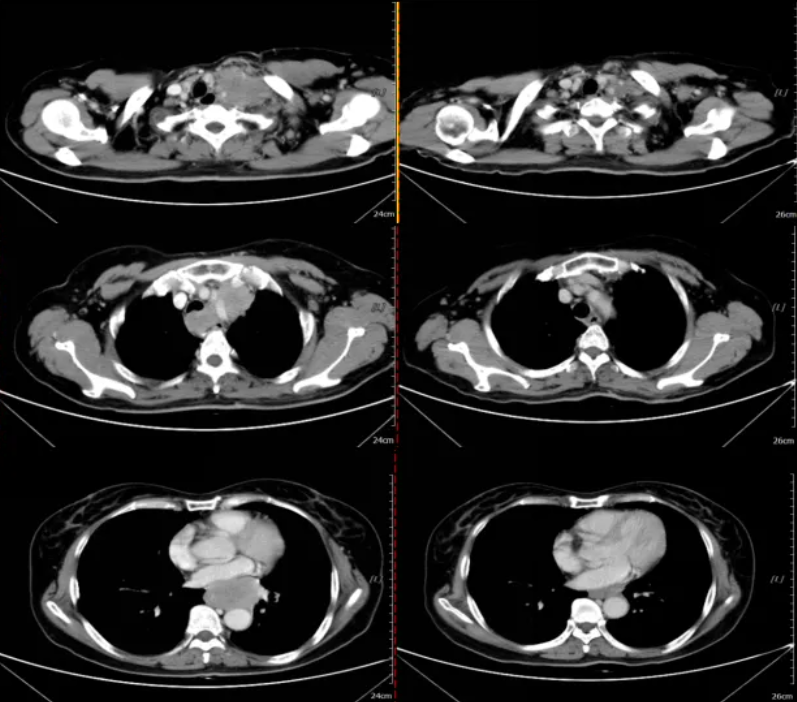

图4 一线治疗2周期后疗效评估为大PR(左:2019-11-7;右:2019-12-25)

图5 一线治疗后进展(左:2020-7-27;右:2021-3-15)

图6 二线治疗后疗效评价为PR(左:2021-3-15;右:2021-4-6)